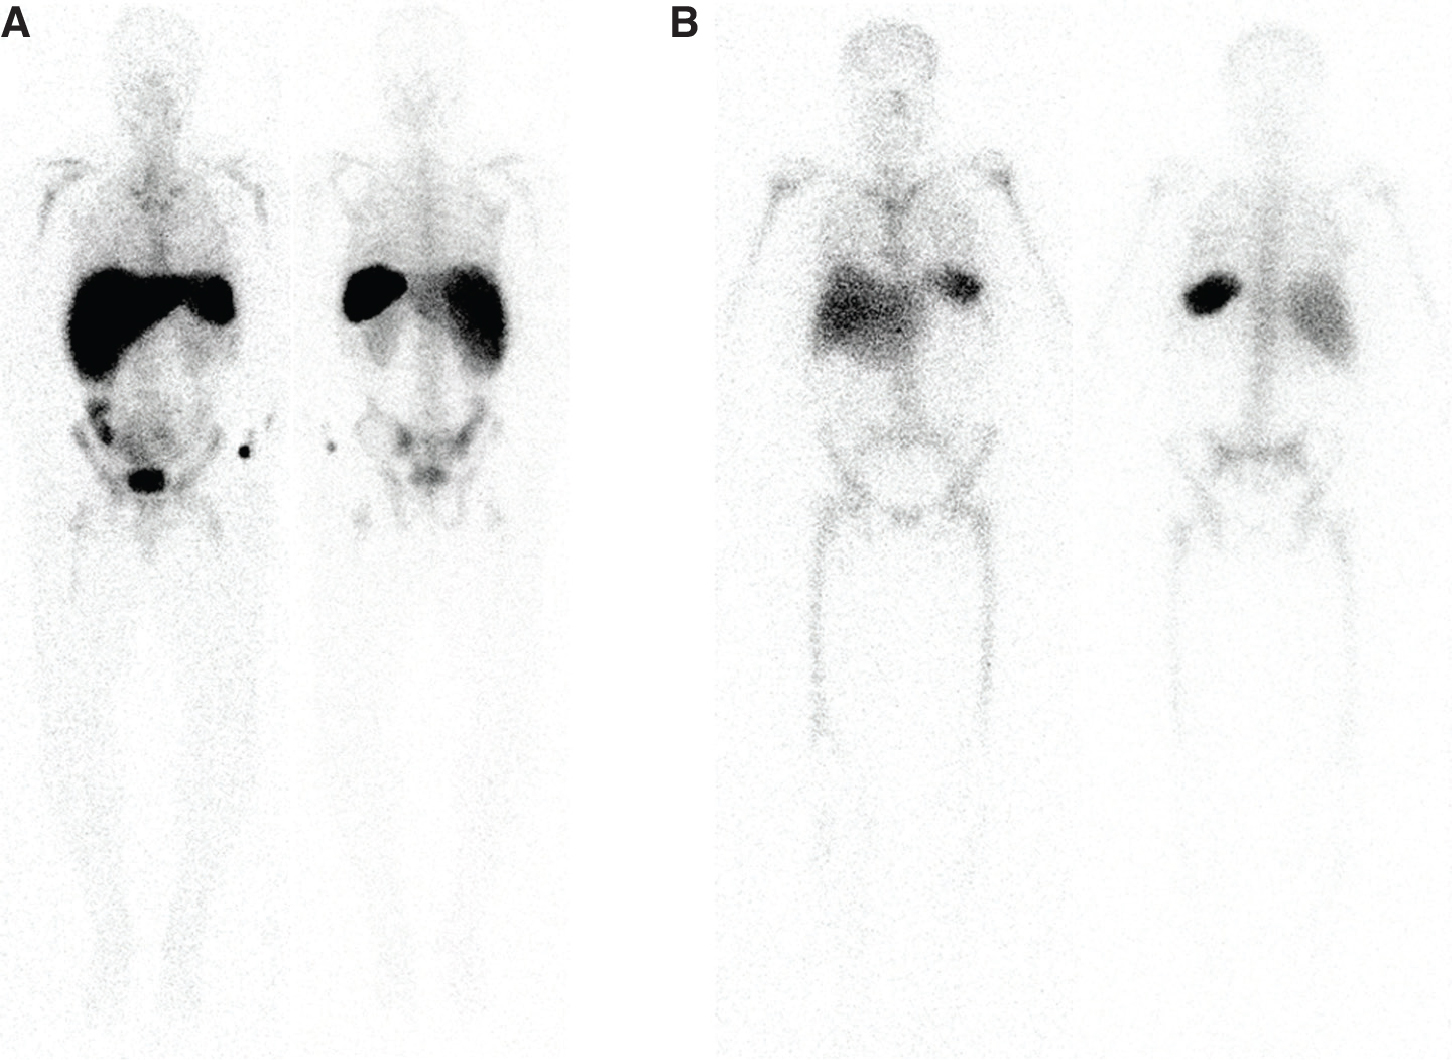

The mechanism of localization of 67Ga-citrate is not well understood but has been postulated to reflect iron metabolism. 67Ga-citrate has a half-life of 78 hours, is cyclotron produced, and decays by electron capture, with the critical organ being the colon. Its photopeaks are 93, 185, 300 and 394 keV. Given the long half-life, this agent is not recommended for pediatric patients. Historically, 67Ga-citrate has been used for the imaging of lymphoma, which occasionally helps in the incidental detection of other tumors. In the past, 67Ga-citrate was the preferred agent for the study of sarcoidosis, which is now better evaluated with 18F-fluorodexyglucose (18F-FDG) positron emission tomography (PET). In addition, 67Ga-citrate could be used in the setting of vertebral osteomyelitis since it has better overall performance, however, 67Ga-citrate is falling out of favor due to its long half-life, relatively high radiation dose, and unfavorable imaging characteristics (1, 2). Figure 1 shows normal biodistribution of 67Ga-citrate.

Fig 1

Figure 1 Normal distribution of 67Ga-citrate. Anterior and posterior planar images of the head, neck, chest, abdomen, pelvis and proximal lower extremities demonstrate normal biodistribution of 67Ga-citrate.